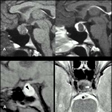

Tumores hipotálamo-hipofisariosBy admin on September 18th, 2008 | 40 Comments

Tumores hipotálamo-hipofisarios Los tumores localizados en el área hipotálamohipofisaria cursan con manifestaciones específicas dependiendo de las alteraciones endocrinas que causen. Asimismo, debido a su carácter de lesiones ocupantes de espacio limitadas a una región muy circunscrita, estos tumores presentan una variedad de manifestaciones comunes e independientes de sus manifestaciones... -